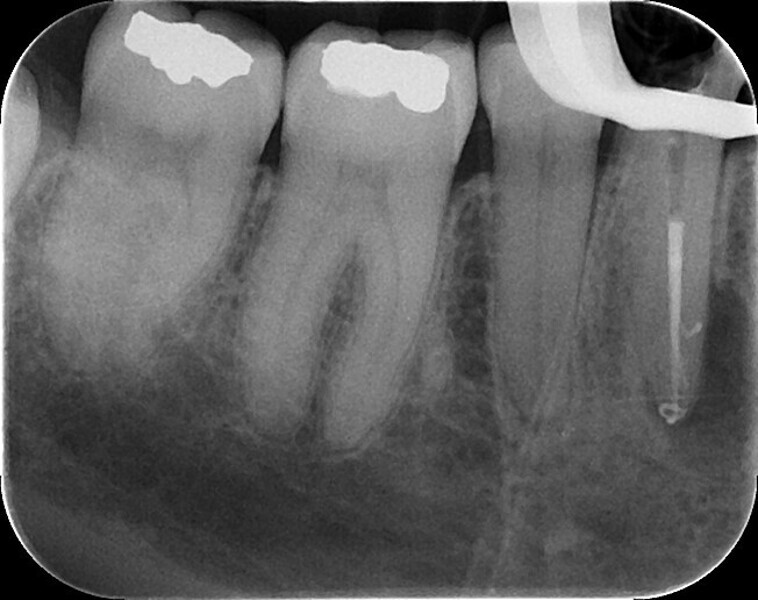

Shaping a Type V mandibular premolar with VDW.ROTATE